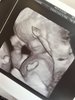

U nas wieści super. Wszystko rozwija się idealnie. Wyniki prenatalnych tez wszystkie piękne. Bardzo niskie wskaźniki chorób. Cała anatomia idealna. Jedyne co to przez ta moja żółta wydzielinę dostałam skierowanie na badanie do onkologa zeby obejrzał szyjkę pod mikroskopem zeby na 100% upewnić się ze wszystko jest w porządku bo posiewy wyszły dobrze. Załączam fotki w 3D

.

Następna wizyta za 3 tygodnie i wtedy podobno już na 100% płeć mi powie![]()